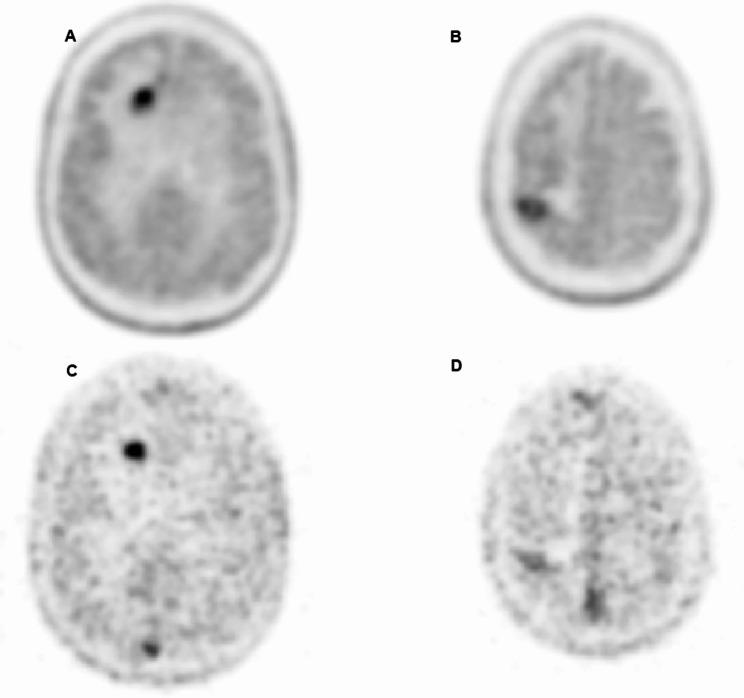

It is difficult to distinguish between the brain metastasis progression (BMP) and brain radionecrosis (BRN) on the basis of F-3,4-dihydroxyphenylalanine positron emission tomography/computed-tomography (F-FDOPA PET/CT) data. The advent of silicon photomultiplier (SiPM) PET technology makes it possible to study dynamic volumes and potentially improve diagnostic accuracy. We developed a method for processing F-FDOPA PET/CT in the differential diagnosis between BMP and BRN. The method involves a short (3-second) sampling time during a 4-minute acquisition on a SiPM-PET/CT machine. We prospectively included 15 patients and 19 metastases. All acquisitions were performed in list mode acquisition for 25 min on a four-ring SiPM PET/CT system. We calculated the ratios between the maximum activity in the lesion's voxel and the mean activity in the contralateral region (VOImax/CLmean) or the mean activity in the white matter (VOImax/WMmean).

RESULTS

Seven lesions were classified as BMP and twelve were classified as BRN. Statistically significant intergroup differences in the VOImax/CLmean and VOImax/WMmean activity ratios were observed for both the clinical volume and the early acquisition. The best performing quantitative variable was the VOImax/CLmean ratio on early acquisition, with a diagnostic accuracy of 94.7%, a sensitivity of 100%, and a specificity of 91.7%.

CONCLUSION

The F-FDOPA PET/CT data acquired a few minutes after the bolus injection confirms its value in differentiating between BMP and BRN, compared to the much longer classic clinical protocol.